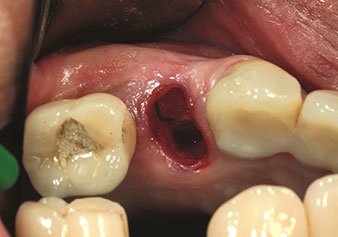

Un’applicazione che viene spesso sottovalutata è l’estrazione atraumatica di radici di denti o frammenti di radici nell’ambito della gestione alveolare. I periotomi sottili, che sono attualmente disponibili in due versioni (EX1 ed EX2 di W&H), possono essere, inoltre, utilizzati per rimuovere con facilità denti che hanno precedentemente subito uno specifico trattamento endodontico o con radici anchilosate. Ne consegue l’estrazione di alveoli in cui i tessuti duro e molle sono entrambi completamente intatti in quanto è generalmente possibile evitare la riflessione.

Ciò pone le basi ottimali per un trattamento con impianto immediato o successivo (Figure 1 e 2 inserite grazie alla gentile concessione del Dott. Torsten Conrad, Bingen a. Rhein).

Foto: © Dott. Torsten Conrad (Bingen am Rhein)